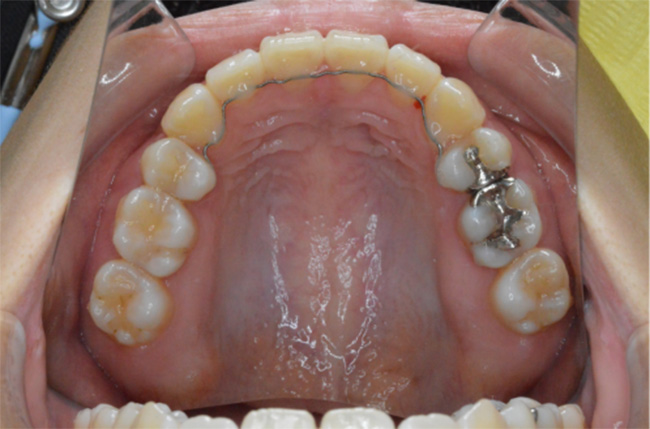

| 治療方法 | 上下顎小臼歯4本抜歯、ワイヤー矯正 |

| 治療内容 | 抜歯のスペースを使用して、上下前歯を後退させた |